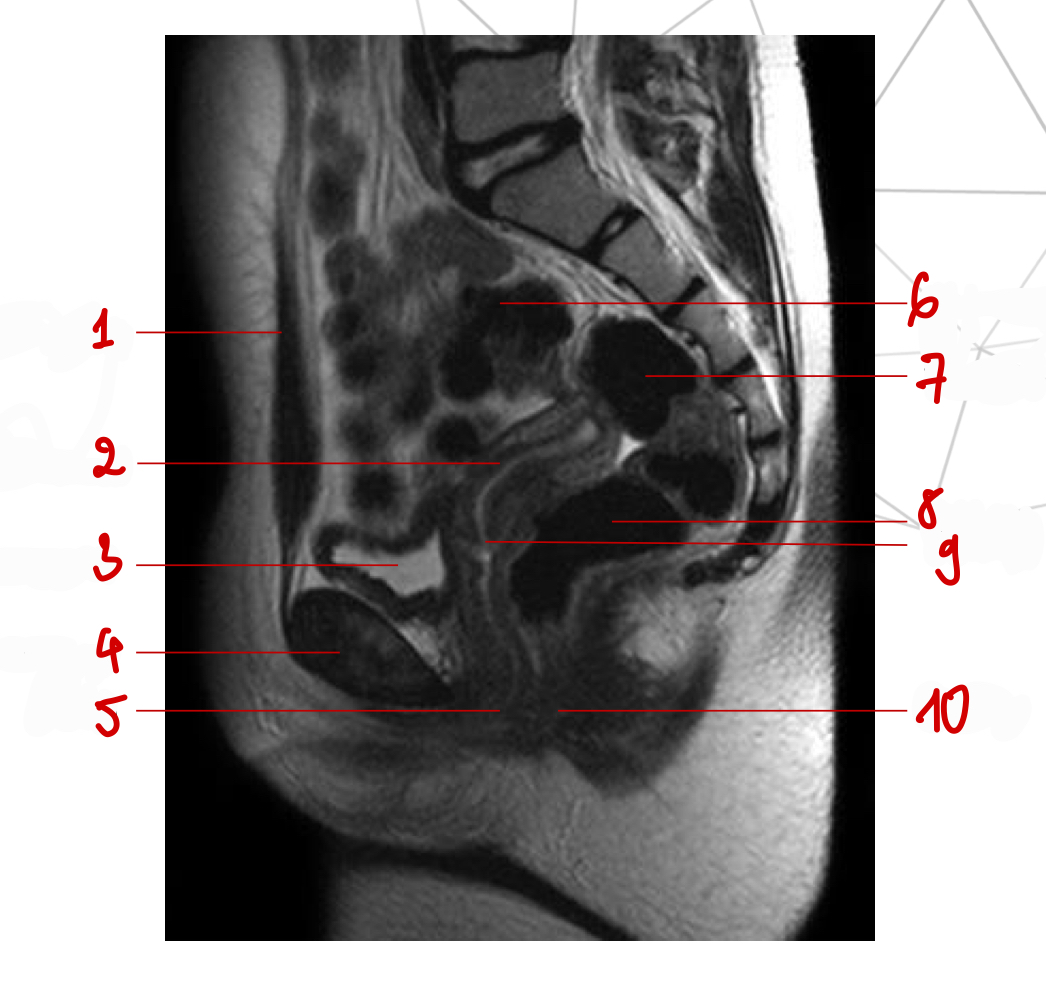

T2w sag, thì nghỉ

Tên chuỗi xung, mốc gp, thì

Mốc gp, chuỗi xung, thì

Thì nghỉ, T2w ax

chuỗi xung, thì, mốc gp

T2 cor, thì nghỉ